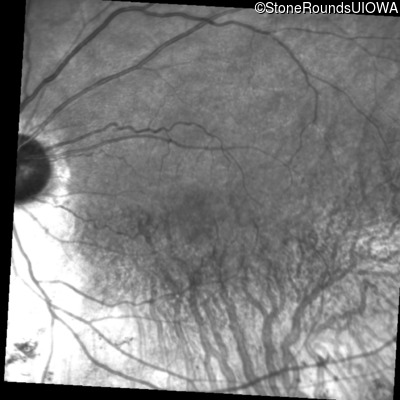

Infrared Fundus Photograph - Right - 20/25 -3

Exemplar

Infrared Fundus Photograph - Left - 20/25 +1

Infrared Fundus Photograph - Right - 20/20

Infrared Fundus Photograph - Left - 20/20